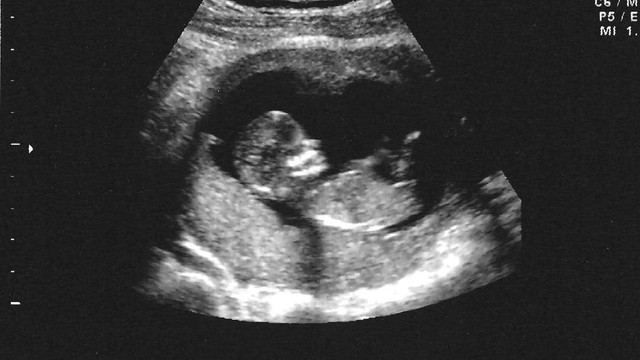

Theo thống kê, tụ dịch dưới màng đệm có thể xảy ra ở khoảng 2% phụ nữ mang thai. Vậy tụ dịch màng đệm bao lâu thì khỏi? Có nguy hiểm không? Cùng tìm hiểu rõ hơn về tình trạng này ở bài viết dưới đây.